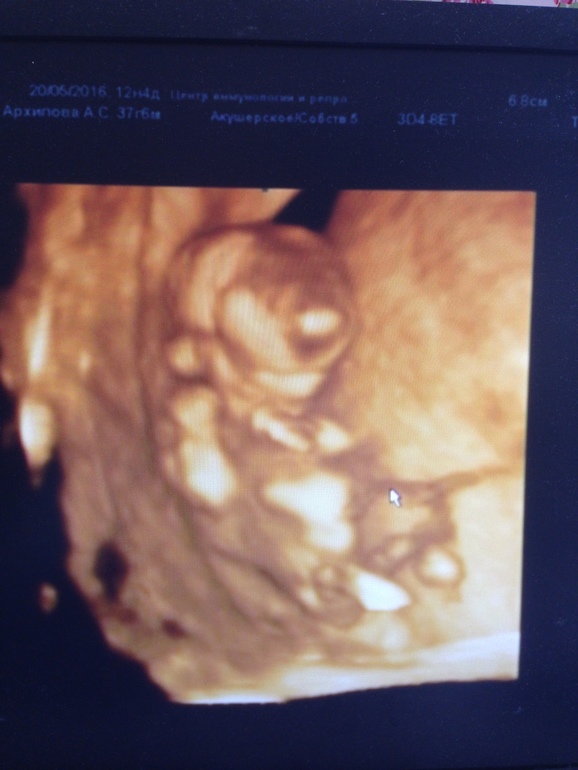

И наш инопланетянин😍😍😍

Ага таки смешные. У меня видео в 3 Д идёт, такая прикольная ручками у лица водит